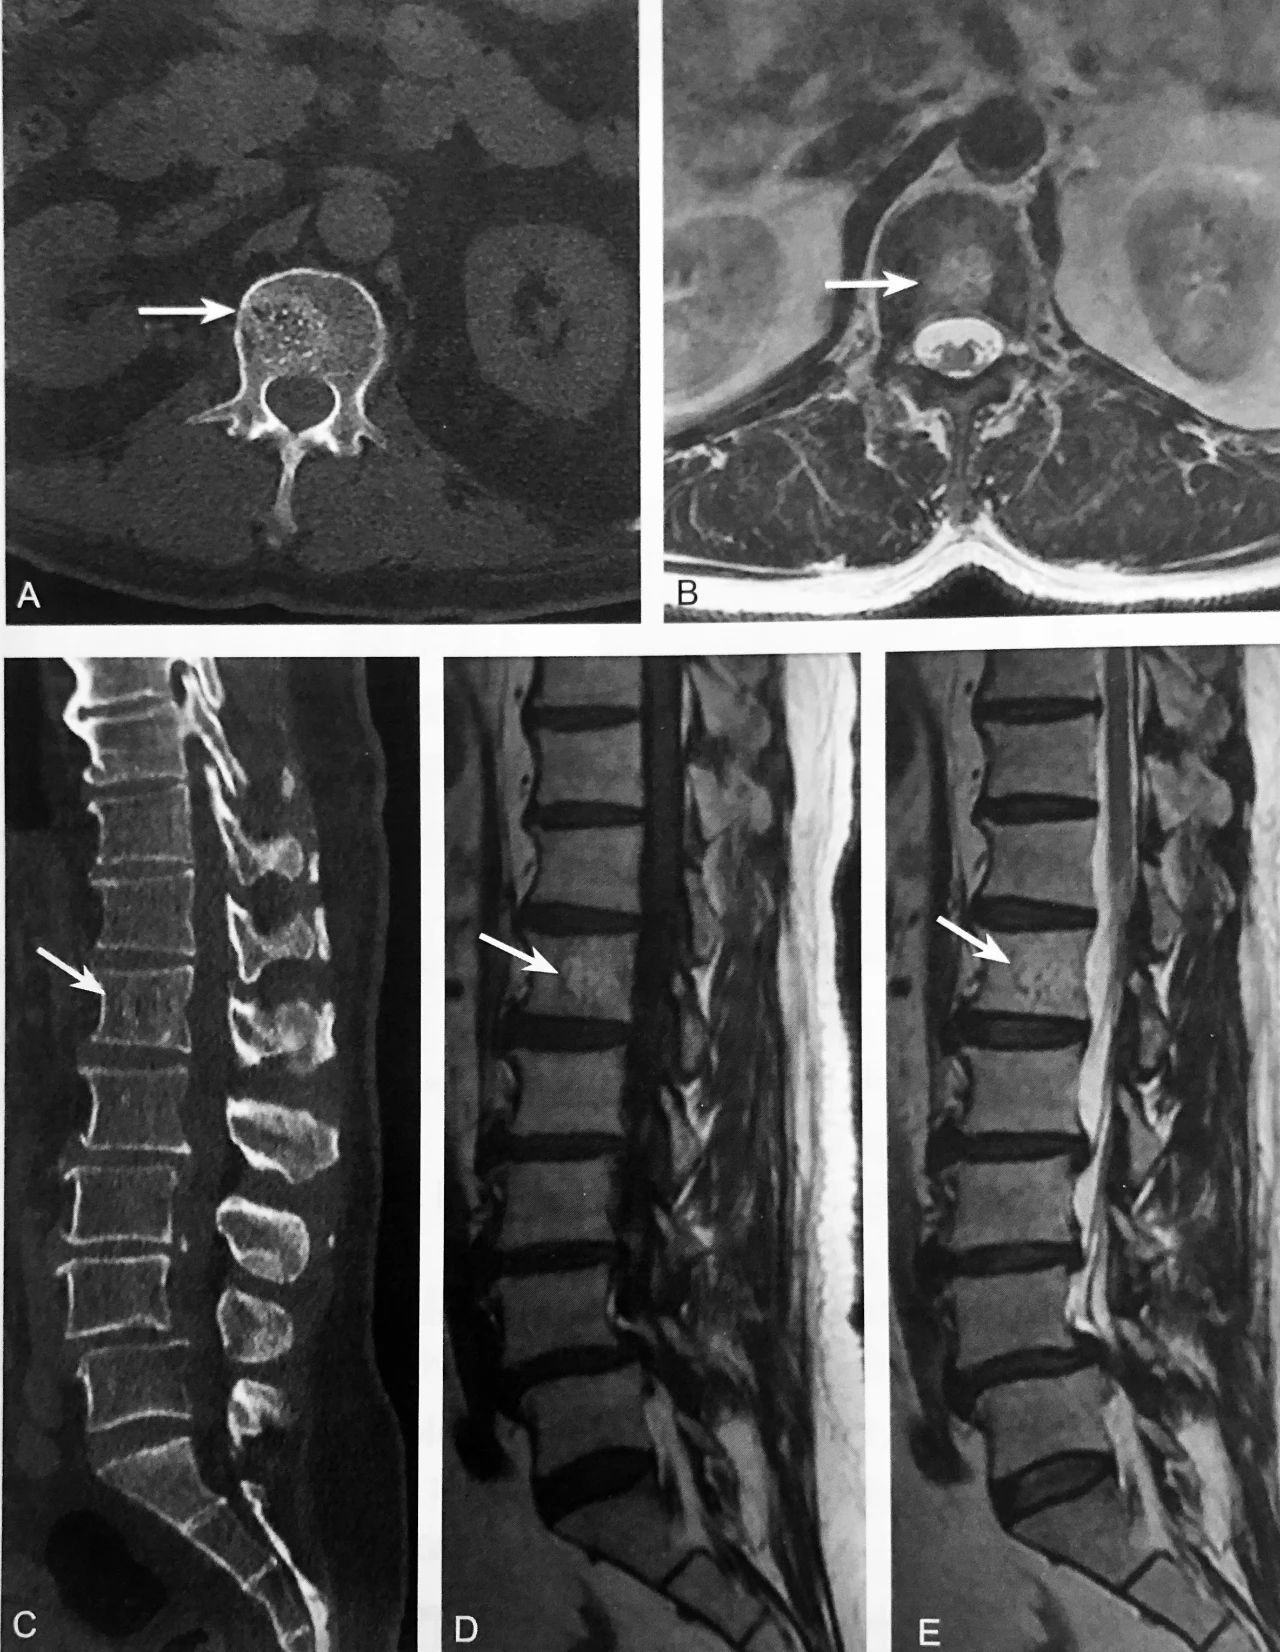

A.腰椎 CT 轴位示椎体内片状低密度区内多发点状高密度影,类似圆点形(箭头);B.T2WI 轴位示椎体内片状稍高信号区内多发点状低信号灶(箭头);C.腰椎 CT 重建矢状位示椎体内骨小梁条状增粗,周围间隔低密度区,呈“栅栏征”改变(箭头);D~E.T1WI 及T2wI 示椎体内片状稍长T2、稍短T1信号,病灶中心及周边见小点状、条状低信号区(箭头)

判读要点:

1、是椎体血管瘤特异性影像征象;

2、在 CT 轴位图像观察,呈圆点样高密度,周围脂肪样低密度;CT 矢状位或冠状位呈灯芯绒征或栅栏征;

3、MRI 有助于观察增粗骨小梁周围脂肪结构。